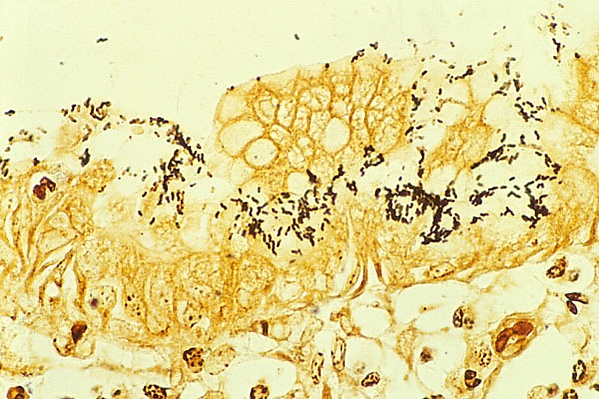

Показана синергетичность действия генов babA2, cagA, и s1 vacA при патологическом процессе, вовлечённом в метаплазии кишечника[38]. Продукты генов cagA и babA2 идентифицируются иммуногистохимически, гистологически и при помощи in situ гибридизации при метаплазии кишечника и злокачественных новообразованиях желудка, ассоциированных с геликобактерной инфекцией и могут служить возможными диагностическими маркерами[39].

Первым методом, который стали использовать для диагностики геликобактерной инфекции, является гистологический метод. Материалом исследования являются клетки тканей, полученных с помощью биопсии, производимой во время эндоскопического обследования желудка и двенадцатиперстной кишки. Специфичность гистологического метода может достигать 100 %, а чувствительность — 91-93 %, ввиду того, что бактерии неравномерно распределены по слизистой оболочке желудка: взятие производится из мест с максимально выраженной гиперемией и отёком, при этом взятие из дна язв и эрозий, а также из их краёв, является ошибкой, поскольку в них нет эпителиальных клеток, необходимых для колонизации бактерий. Кроме того, приём антибиотиков и ингибиторов протонной помпы может трансформировать бактерии из спиралевидной формы в кокковую, которую невозможно выявить с помощью обычной микроскопии[51].